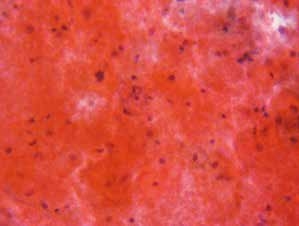

图7-13 不满意样本(高倍、液基、巴氏染色)

高倍显示大量中性粒细胞,此例无足够数量的鳞状上皮细胞,但仍需报告可见大量的炎细胞。